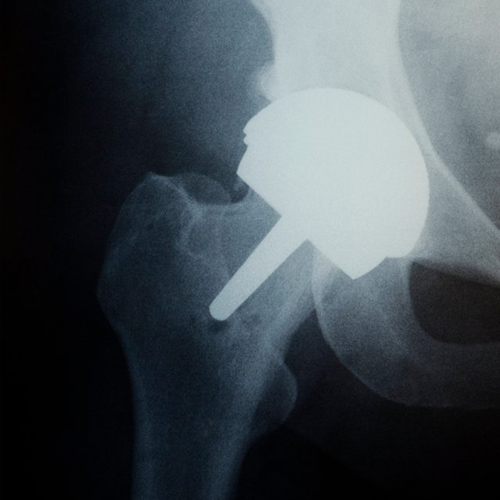

주로 무릎, 엉덩이, 어깨 관절에서 시행됩니다.

인공고관절수술 당일부터 3개월간은 다리를 30도 정도 벌린 자세를 유지해야 수술 부위의 안정성을 가질 수 있습니다. (누울 때나 앉을 때 항상 유지)

수술 당일부터 수술 후 3일차까지는 상체를 점진적으로 세웁니다.

(당일 45도, 2일째 60도, 3일째 90도)

수술 후 2주차부터는 목발을 사용하여 보행하며 퇴원이 가능하며, 수술 후 6개월째에는 정상적인 생활 및 스포츠 활동까지 가능해집니다.